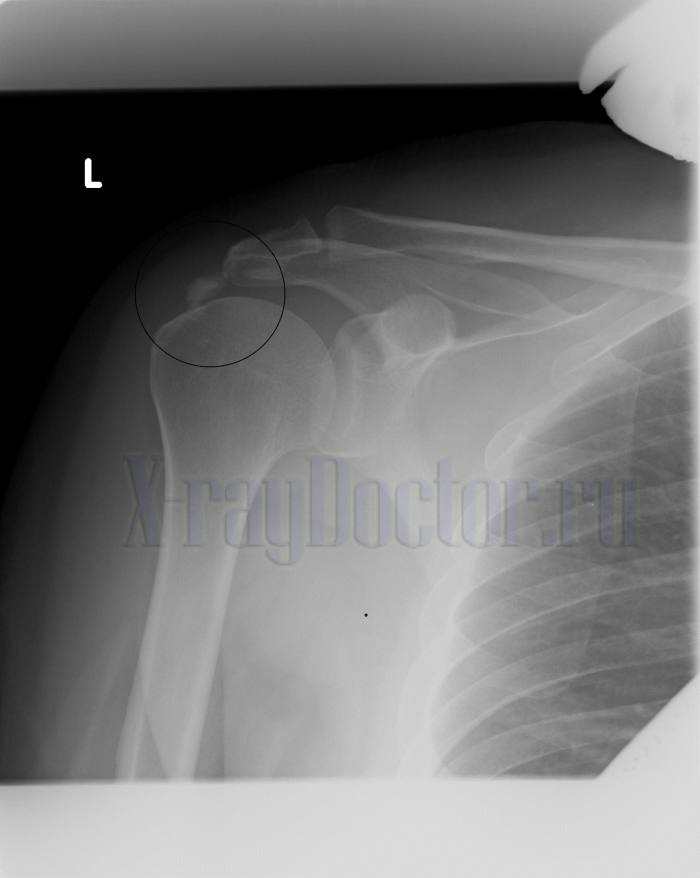

Рентгеновский снимок при плечелопаточном периартрите

Протокол описания: На представленной рентгенограмме правого плечевого сустава визуализируется сужение суставной щели и субхондральный